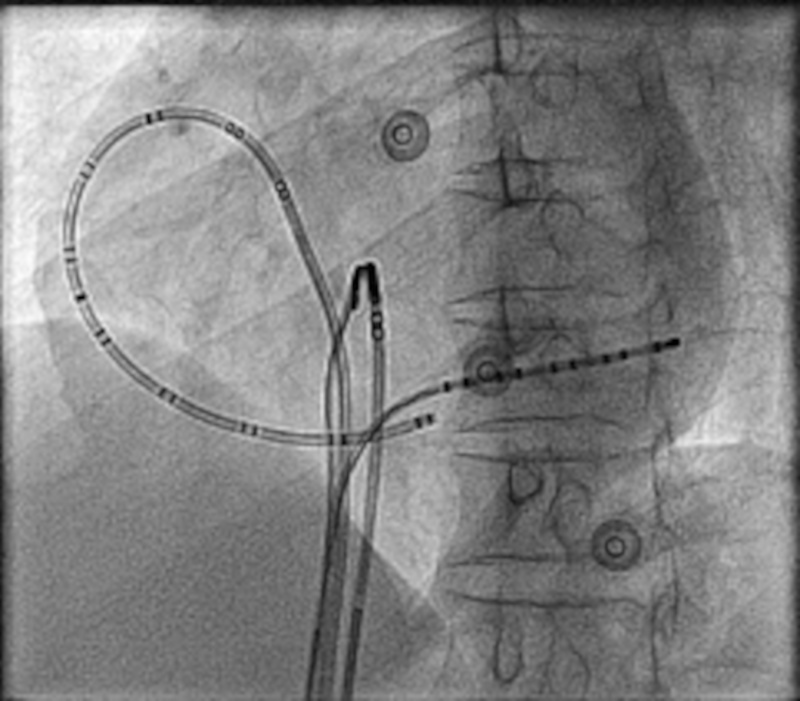

entrainment_three_sites.png

Miyazaki H, Stevenson WG, Stephenson K, Soejima K, Epstein LM. Entrainment mapping for rapid distinction of left and right atrial tachycardias. Heart Rhythm. 2006 May;3(5):516-23. doi: 10.1016/j.hrthm.2006.01.014. Epub 2006 Feb 28. PMID: 16648054.